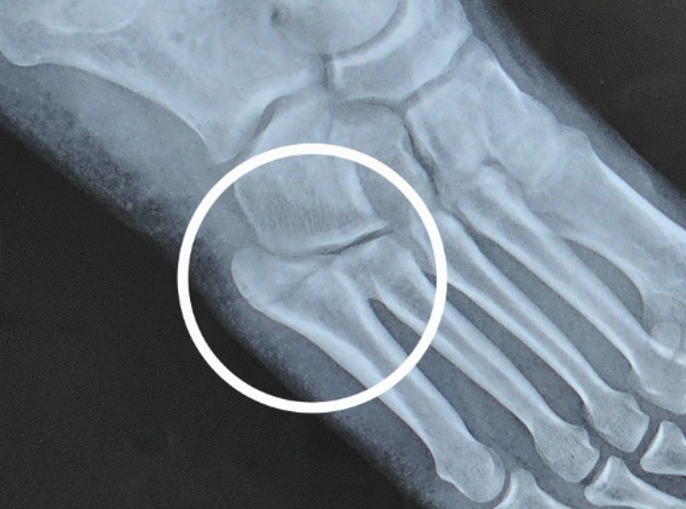

발가락 뼈에 금이 감 - 골절(사진有), 뼈도 원래 붓나요?

발가락이지만 돌출된 발가락 말고 발등? 발날? 쪽으로 새끼발가락 긴 발가락이 골절되었고

엑스레이 상에는 아물고 있지만 덜 아문 상태입니다.

저렇게 톡 튀어 나와 있고 다친 발은 오른발인데 왼발과 비교해보면 확실히 튀어나와 있습니다.

위 사진 부위가 복사뼈처럼 톡 튀어나와 있고 일반 혈액으로 붓기라고 하기엔 딱딱해서 문의드립니다.

• 1번 째 사진